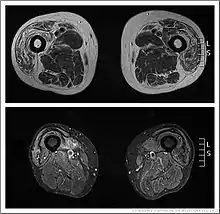

Elevated creatine kinase (CK) levels in the blood (at most ~10 times normal) are typical in sIBM but affected individuals can also present with normal CK levels. Electromyography (EMG) studies display variable abnormalities such as increased insertional activity,[26] increased spontaneous activity (fibrillation potentials and sharp waves),[1] and large/broad or short/narrow motor unit potentials.[1] On EMG, recruitment patterns can be reduced or increased. Findings can vary even within the same muscle of an affected individual.[1] Muscle biopsy may display several common findings including inflammatory cells invading muscle cells, vacuolar degeneration, and inclusion bodies of aggregations of multiple proteins.[27] sIBM is a challenge to the pathologist and even with a biopsy, diagnosis can be ambiguous.[28]

Muscle imaging can help establish the pattern of muscle involvement and selection of a biopsy site.[1]